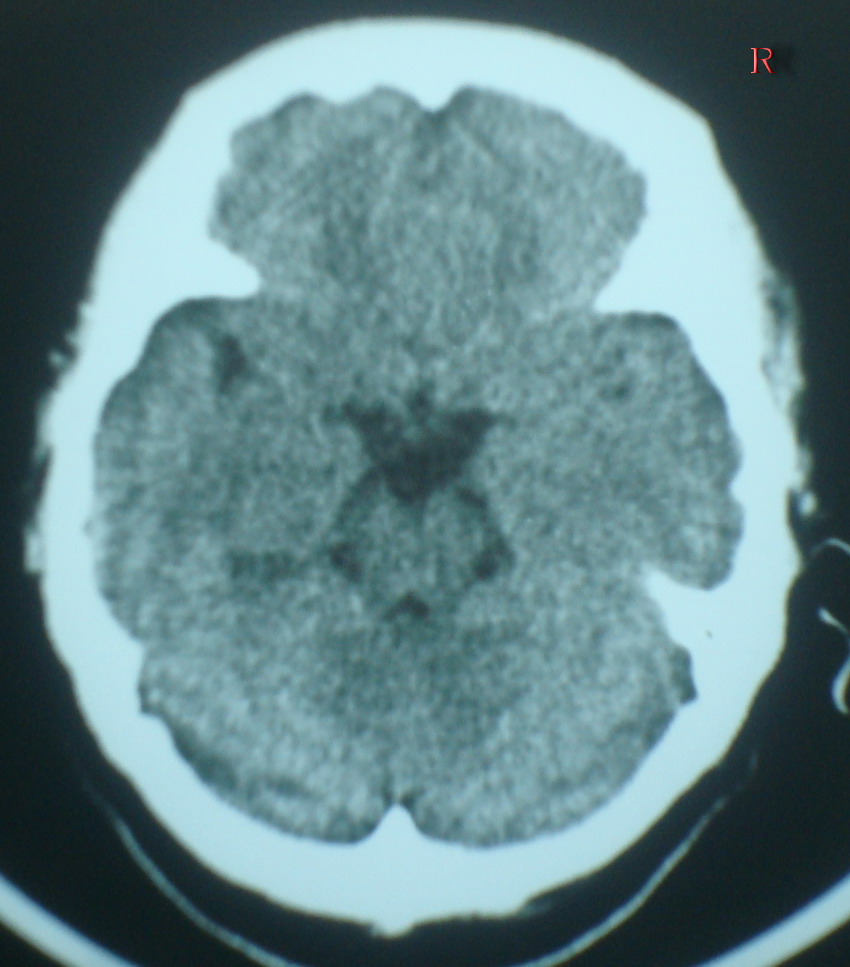

标题: CT19025:女,60岁,突感头痛,忘事两天 [打印本页]

标题: CT19025:女,60岁,突感头痛,忘事两天

右侧颞顶叶交界区片状低密度灶;建议行进一步检查。

以下是引用随光逐影在2009-3-25 21:14:00的发言:[br]右侧颞顶叶交界区片状低密度灶;建议行进一步检查。

右侧颞顶叶交界区片状低密度灶;建议行进一步检查。-----支持!

右侧颞顶叶交界区片状低密度灶;建议行进一步检查.